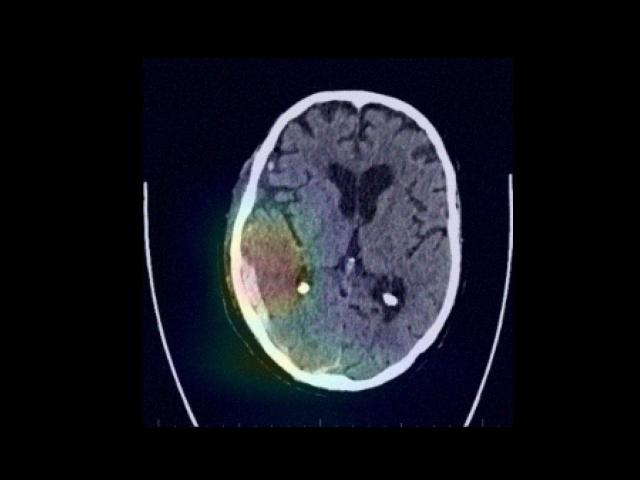

Sample Gallery